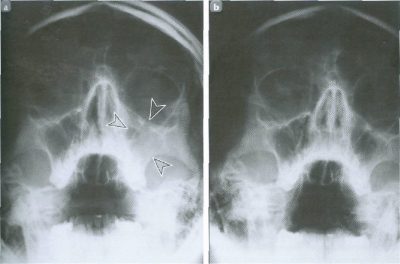

Для наиболее точного определения синусита применяется метод рентгеновского исследования. В случае локализации очага воспаления в гайморовой пазухе, пациенту делается пункция с последующим лабораторным исследованием извлеченной слизи. Компьютерная томография как метод диагностики действенна, если синусит вызван иными (не воспалительными) причинами, например, образованием кисты или искривлением перегородки.